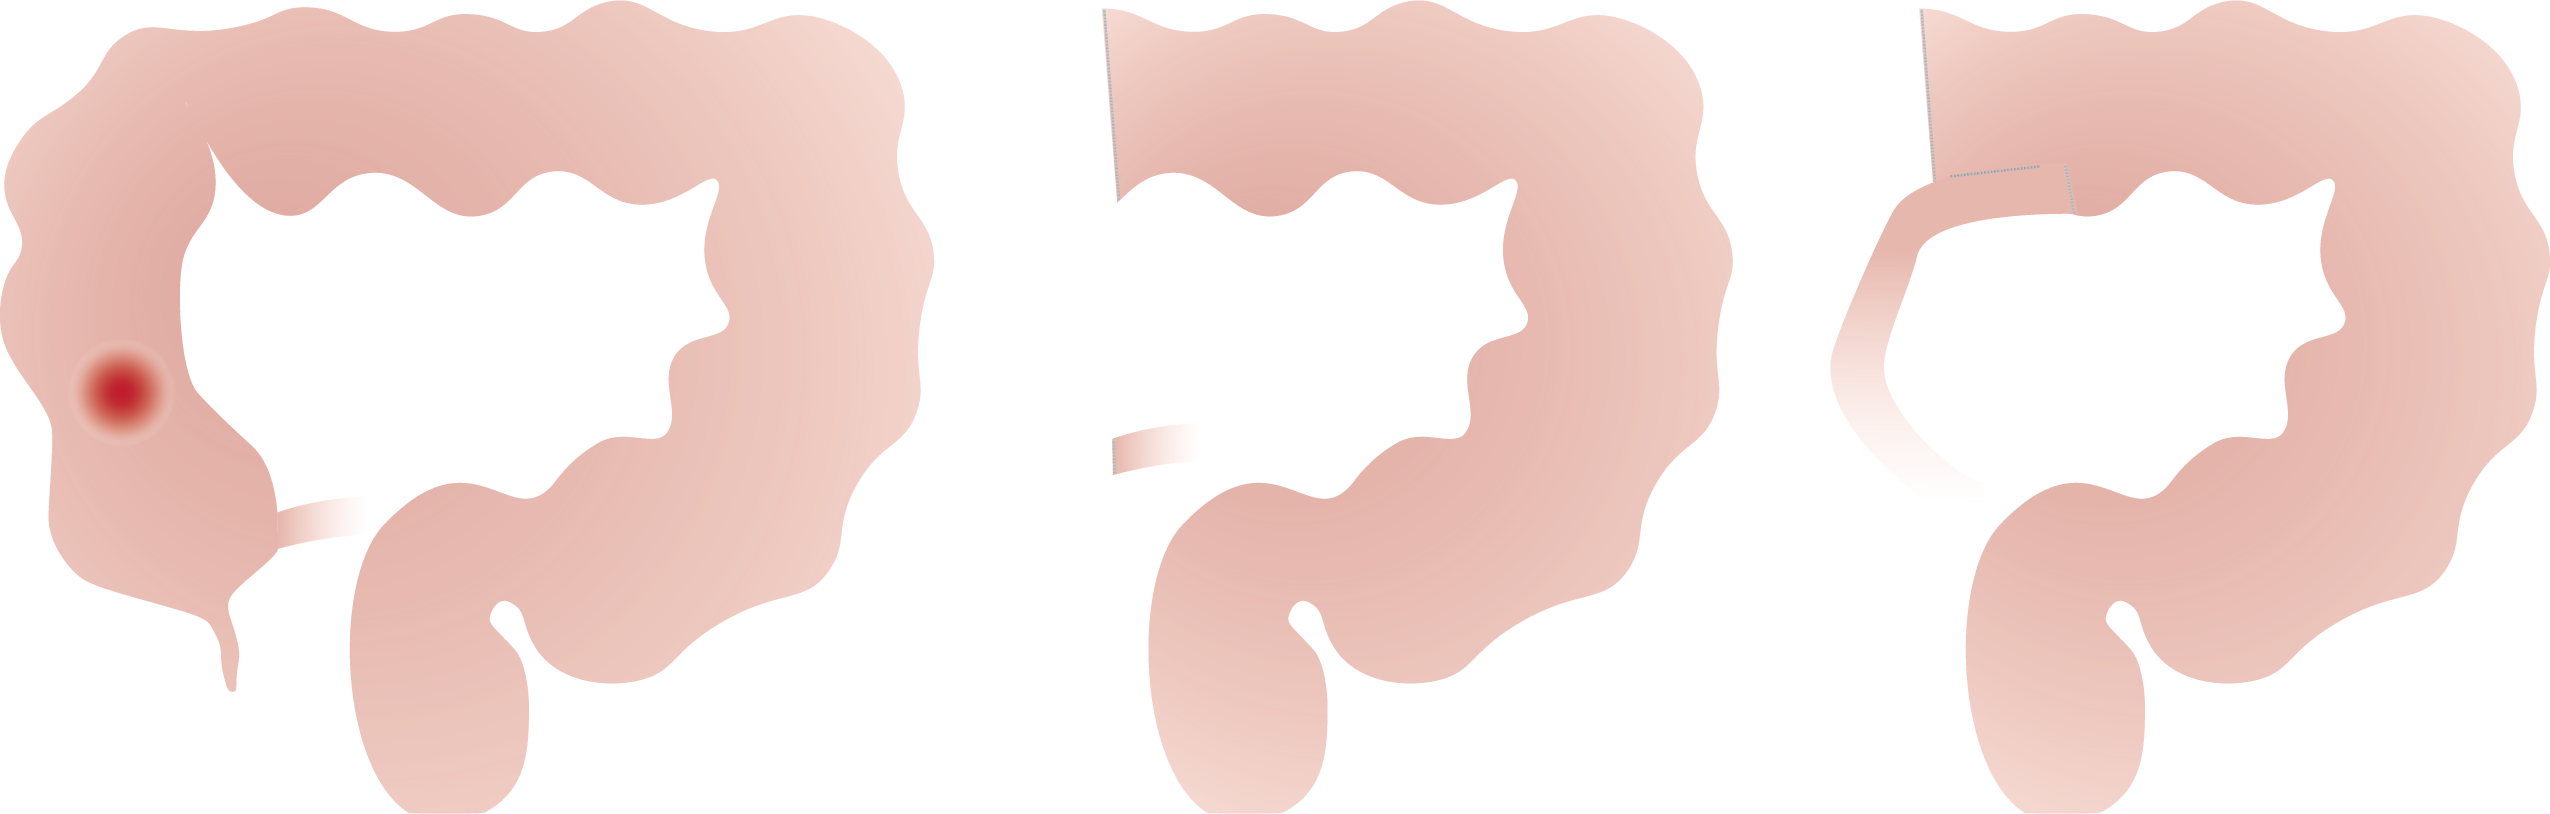

Naargelang de plaats van de aandoening spreekt men van een:

• Linker hemicolectomie (colectomie = verwijderen van dikke darm, hemi = half) en sigmoidectomie (wegnemen van het voorlaatste deel van de dikke darm).

• Rechter hemicolectomie (colectomie = verwijderen van dikke darm, hemi = half).

• Rectum resectie (= verwijderen van de endeldarm zonder de anus).

• Rectumamputatie (= verwijderen van de endeldarm met de anus).

• Totale colectomie (= verwijderen van de hele dikke darm met eventueel dunne darm 'pouch').

Na het verwijderen van het aangetaste stuk darm wordt een nieuwe verbinding gemaakt tussen twee gezonde stukken darm en is het belangrijk dat deze goed gaat genezen.